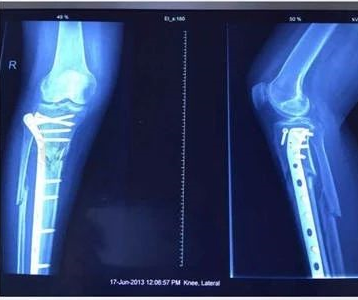

骨折延迟愈合

术后九个月未愈合 冲击波治疗后二个月

按骨折的部位和类型,经过治疗后,未能在平均时间内愈合,骨折断端仍未出现骨折连接,称为骨折延迟愈合。ESWT 具有成骨作用,在治疗骨折延迟愈合方面应用越来越广泛,治疗胫骨、跖骨、股骨等骨折延迟愈合时,总体有效率 70%~90%.